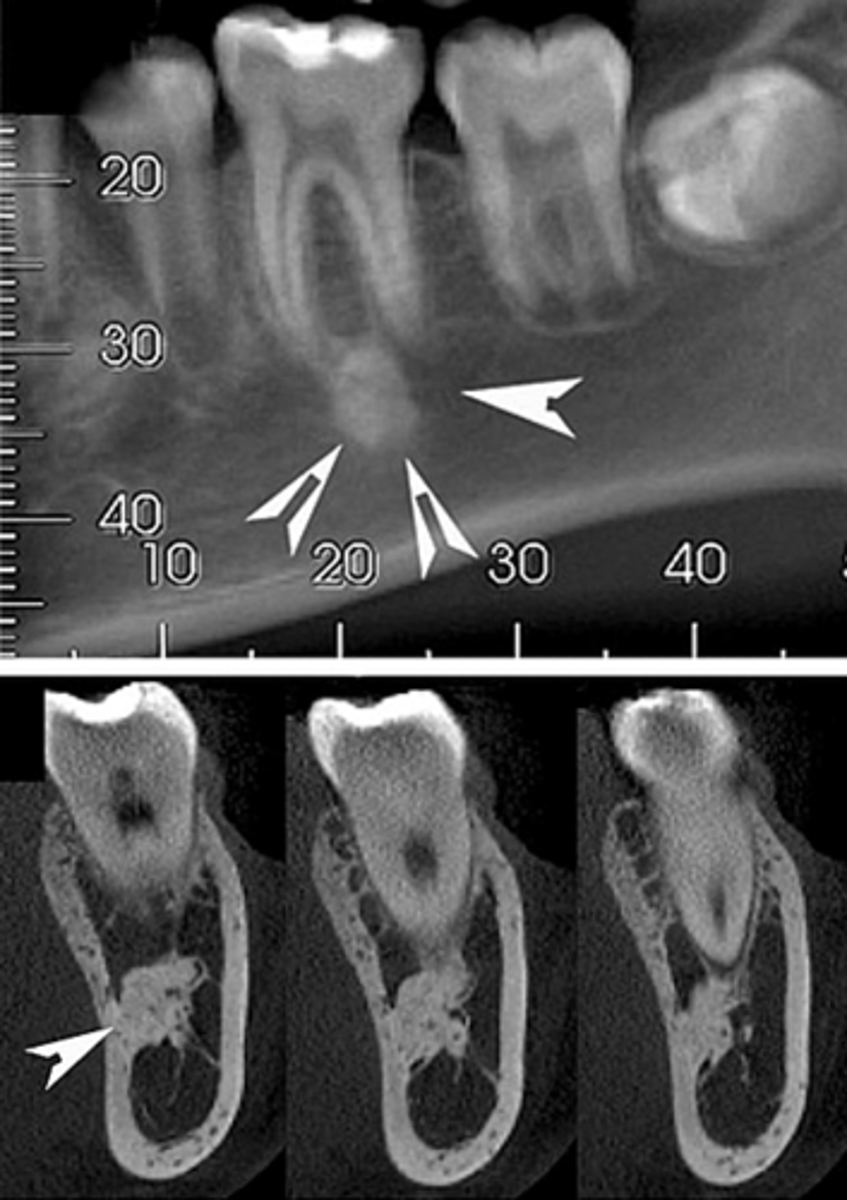

What does a Benign Cementoblastoma appear like on radiograph?

Wheelspoke pattern

What type of teeth are affected by Benign Cementoblastoma?

Vital teeth

What growth is associated with Benign Cementoblastoma?

Bulbous growth at apex

What is a characteristic of Benign Cementoblastoma on the tooth root?

External resorption of root